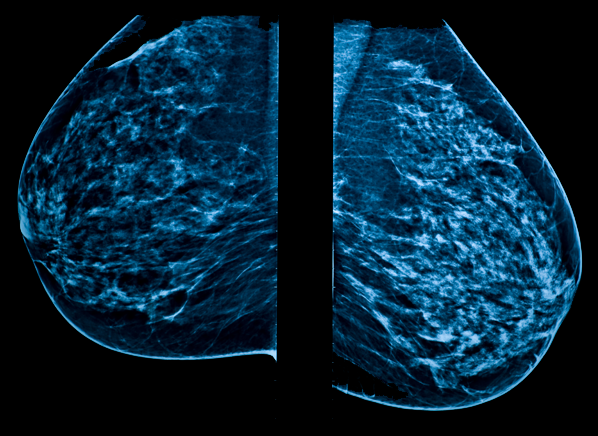

Measuring HER2-Receptor Expression In Metastatic Breast ... from www.thno.org The test has only a limited ability to detect small tumors. The scan is painless and takes about 10 to 30 minutes. Mammograms take advantage of the fact that most of the female breast is fat tissue, so it's relatively transparent to the low doses of radiation used in mammography. If you have a condition like cancer , heart disease , emphysema , or liver masses, ct scans can spot it or help. The term tomography comes from the greek words tomos (a cut, a slice, or a section) and graphein (to write or record). A sentinel lymph node biopsy may first be performed to determine whether cancer has spread to the lymph glands under the arm. Additionally, a diagnostic scan only tells part of the story. Staging tells the doctor how big a cancer is and whether it has spread.

It tends to do more. Ct scans are most often an outpatient procedure. The scan is painless and takes about 10 to 30 minutes. Do ct scans detect breast cancer? This helps determine whether or not the cancer can be removed with mastectomy. A ct scan may be used to look for tumors in organs outside of the breast, such as the lung, liver, bone, and lymph nodes. A ct scan can help doctors find cancer and show things like a tumor's shape and size. Therefore, ct scans can lead to a false negative this can negatively impact your ability to get any treatment at all Radiologists use both ct and mri to detect and monitor cancer. But the patient is also given a nuclear medicine bone scan to see if the cancer has spread to the the bones, and also a liver ultrasound or ct scan to check for liver metastasis. Learn how doctors choose which technique to use. Knowing the stage helps your doctor decide which treatment you need. No indications in lymph nodes, but will check those as well.

Doctors use a computed tomography (ct) scan, also called a cat scan, to find cancer. A ct scan may be used to look for tumors in organs outside of the breast, such as the lung, liver, bone, and lymph nodes. Ct scans can detect bone and joint problems, like complex bone fractures and tumors. A naf pet/ct is more sensitive for bone metastases than a typical bone scan, but also detects more benign findings, too, thus it is less commonly used. However, your doctor may call this a pet scan. If you have a large breast cancer, your doctor may order a ct scan to assess whether or not the cancer has moved into the chest wall. Each imaging method has strengths that make it appropriate for a particular reason. When a breast cancer has been diagnosed, some people have a ct scan of their chest and tummy (abdomen) to stage the breast cancer. Are you preparing to have this procedure soon? Some organs are more sensitive to radiation than others. Ct scans are most often an outpatient procedure. Therefore, ct scans can lead to a false negative this can negatively impact your ability to get any treatment at all Additionally, a diagnostic scan only tells part of the story.